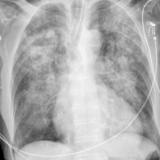

Heart failure

Album: Heart failure

Date: 11/05/2005

Size: 24 items

Views: 57217